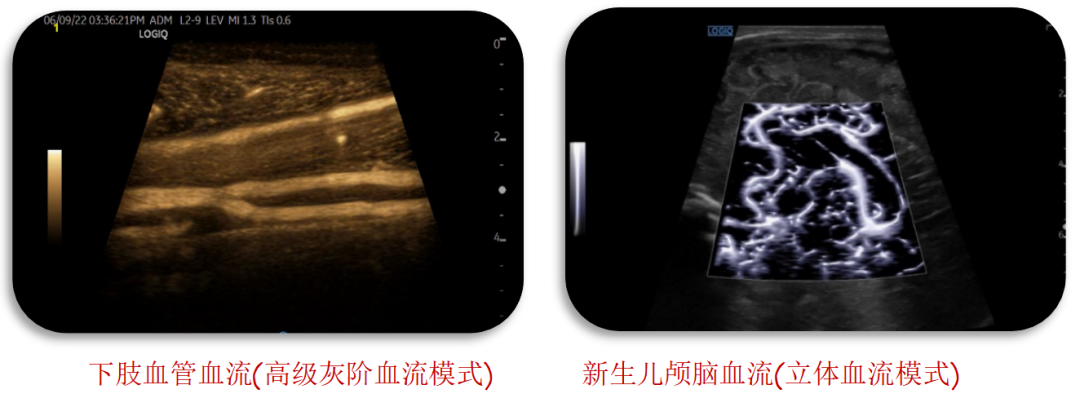

穿透力更强,分辨更精准

冰晶探头技术可在获得更高分辨力的同时兼顾高穿透力,帮助医师及时观察到脏器的病变。设备搭配的B-Flow™ 类造影血流和MVI 超微细血流成像,对血流显示能力大幅提升, 可捕捉到组织及病灶的细小血管,可观察到血管中较小斑块,提高临床诊疗能力。同时配备应力式弹性成像,对一些器官的结节,可做弹性成像检查,进一步明确肿物性质。